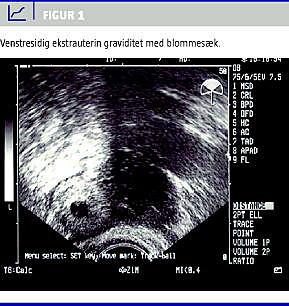

En 33-årig kvinde blev henvist til Gynækologisk Afdeling med nedre abdominalsmerter. Tidligere gynækologisk rask, en provokeret abort for otte år siden, en normal fødsel for tre år siden. Nu spontant gravid med menostasi svarende til uge 6+4. Hun havde gennem nogle dage haft intermitterende venstresidige nedre abdominalsmerter, som nu var tiltaget, og der var forværring ved bevægelse. Der var sparsom vaginalblødning. Objektivt var patienten upåvirket, ved gynækologisk undersøgelse fandtes ømhed og peritonealreaktion over venstre adnex. Ved vaginal ultralydskanning fandtes en venstresidig ekstrauterin gestationssæk med en blommesæk (Figur 1 ) og desuden en moderat mængde fri væske i abdomen. Højre adnex var upåfaldende, og uterus var tom med normalt endometrium.